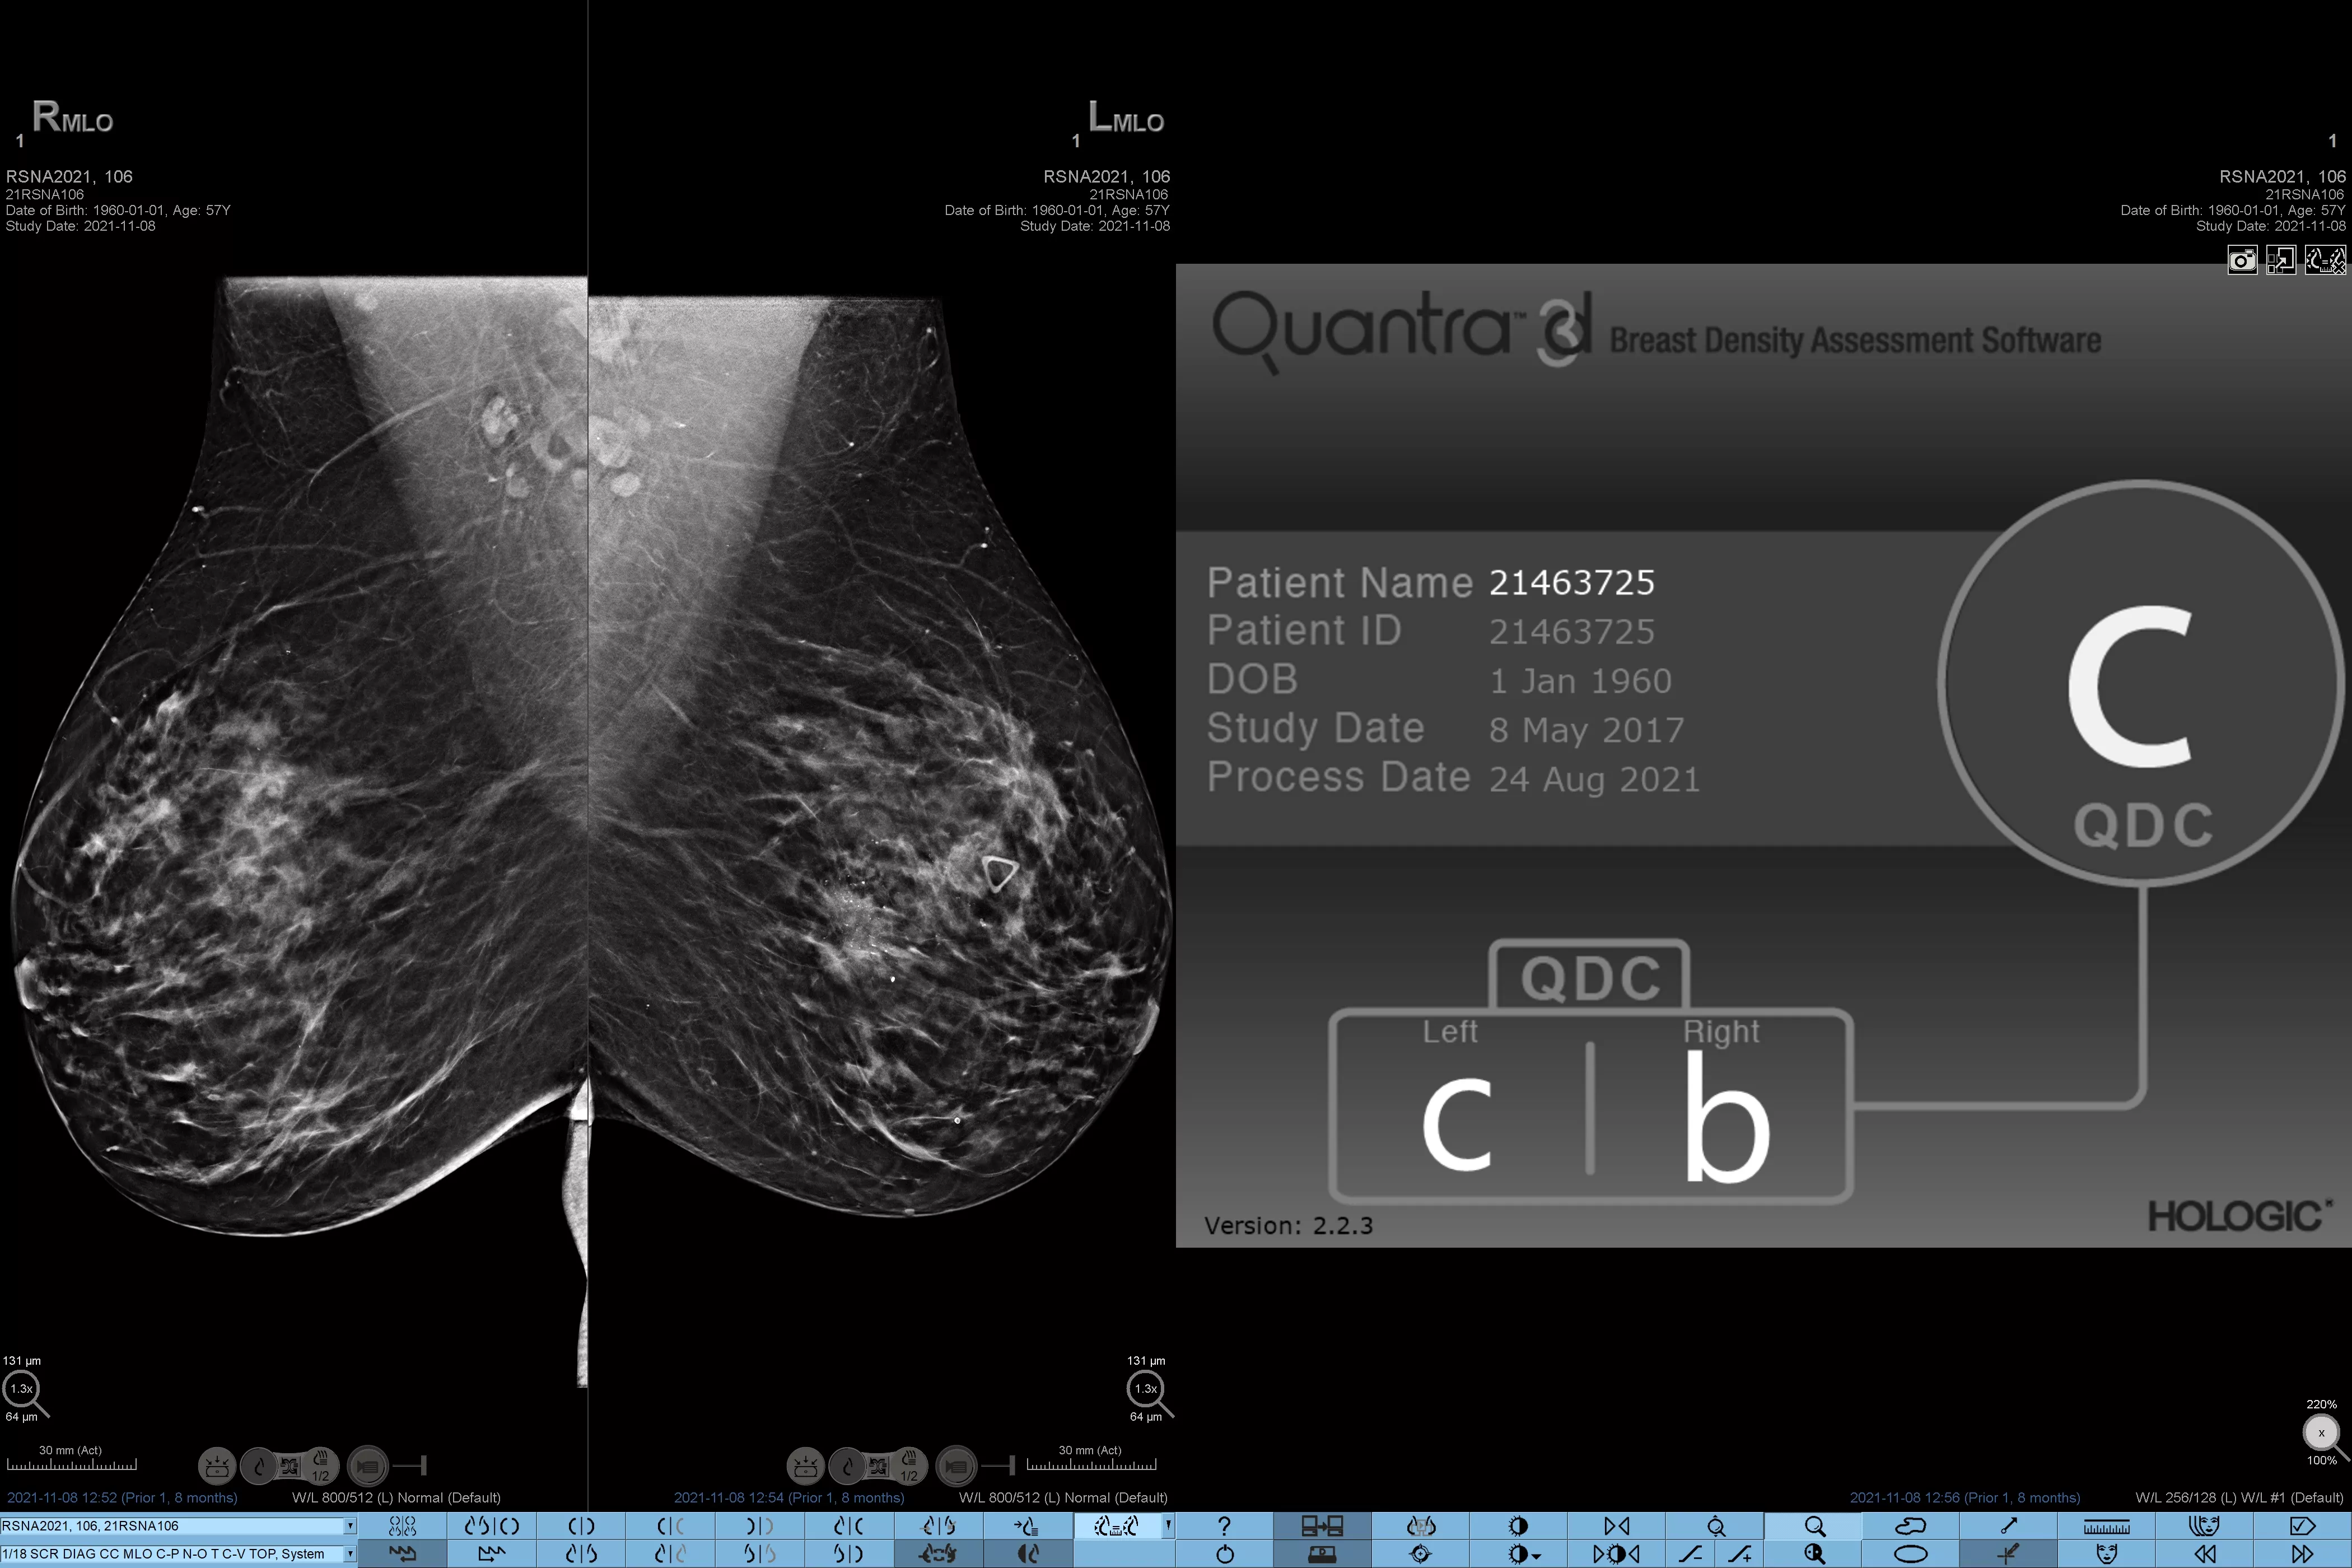

On sait qu’une densité mammaire plus élevée augmente le risque de cancer du sein chez la femme.1 Une analyse précise et objective s’avère donc primordiale. Optimisé par l’apprentissage automatique, le logiciel de la technologie Quantra analyse les images 2D™ et de tomosynthèse pour déterminer la distribution et la texture du tissu parenchymateux. Il classe les seins selon quatre catégories de composition, conformément aux recommandations de l’American College of Radiology (ACR) BI-RADS Atlas 5th Edition.2

Images de mammographies